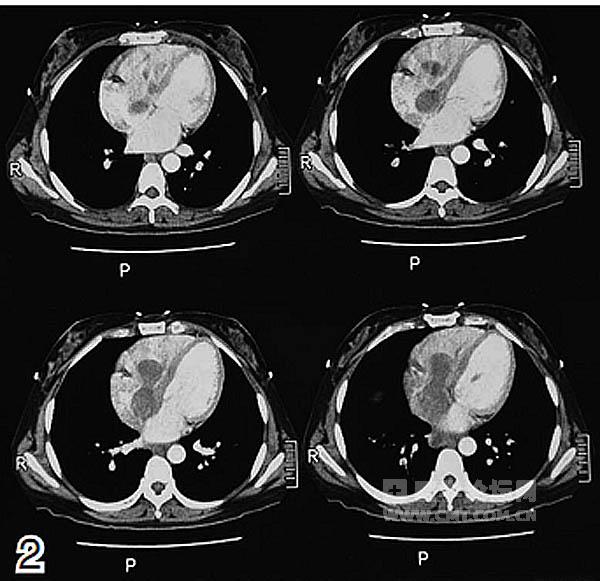

辅助检查:CT示腹盆腔巨大肿块;右侧髂静脉、下腔静脉、右心房及右心室瘤栓形成;右肾、双侧输尿管、膀胱、血管及消化道均受压推移。实验室检查示癌抗原125(CA125)为44.2 IU/ml,神经元特异性烯醇化酶(NSE)为17.0 ng/ml,雌二醇为1486 pmol/L。

放射科:该患者的CT及磁共振成像(MRI)检查显示,腹盆腔内有巨大不规则软组织密度影,边界不清,病灶推压临近肠管、胰腺、右肾及膀胱,右侧髂静脉、下腔静脉、右心房及右心室内可见充盈缺损影,考虑子宫平滑肌瘤病累及下腔静脉及右心房(图1~2)。

心外科:下腔静脉至右心房肿瘤的临床症状出现缓慢且表现不典型,临床表现与静脉阻塞部位和程度有关。早期患者常无明显症状,当瘤体较大时可阻塞下腔静脉或三尖瓣口,血液回流受阻,可出现下肢水肿,腹壁静脉曲张,心悸、气促等表现,瘤体阻塞三尖瓣口还可致体位性低血压、晕厥和猝死。目前超声显示,瘤体自右侧髂静脉分叉水平向上延伸,沿下腔静脉进入右心房并跨过三尖瓣右心室,如果不手术则患者随时面临死亡的风险,但手术风险极大。如进行手术,为防止术中肿瘤脱落,可先行深低温体外循环下开胸取瘤。